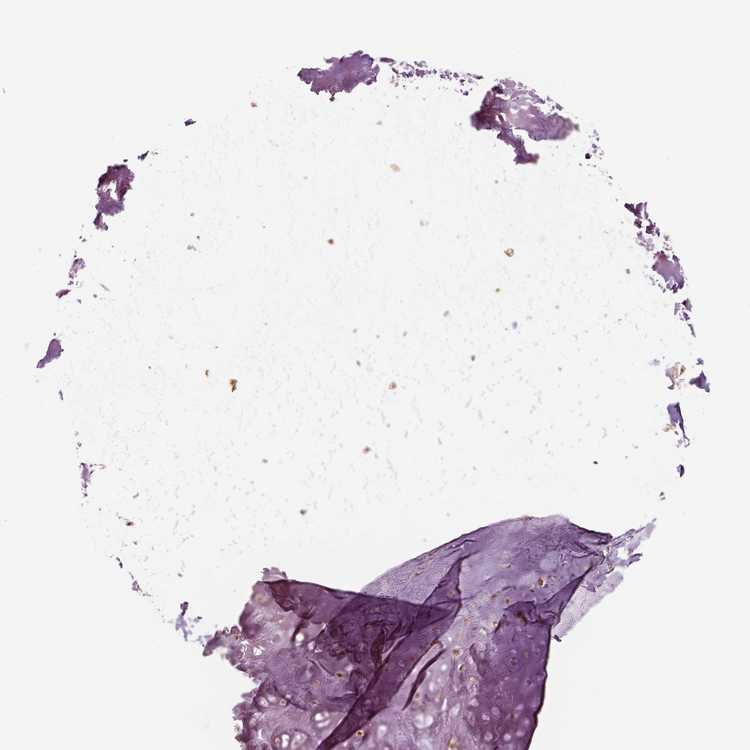

SOFT TISSUE 2 - Antibody stainingi

Antibody staining in the annotated cell types in the current human tissue is reported as not detected, low, medium, or high, based on conventional immunohistochemistry profiling in selected tissues. This score is based on the combination of the staining intensity and fraction of stained cells.

Each image is clickable and will lead to virtual microscopy that enables deeper exploration of all samples and also displays staining intensity scores, fraction scores and subcellular localization as well as patient and tissue information for each sample.

Antibody HPA067740

Fibroblasts Not detected

Peripheral nerve Not detected